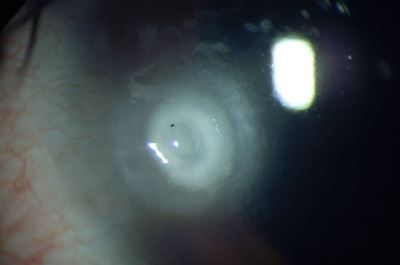

Segmentos Intracorneales: (Anillos): Los segmentos intracorneales son segmentos de acrílico de forma semicircular que se insertan dentro de la córnea en su perifería para dar soporte, regularizar y aplanar la superficie anterior deformada por la ectasia; como efecto secundario corrigen parcialmente la miopía y el astigmatismo inducidos por la deformación. Se insertan a través de un incisión pequeña que se realiza con un laser Femtosegundo o en forma manual, con instrumentos especialmente diseñados para ello; La previsibilidad del resultado refractivo es relativa. Hoy en día se emplean para aplazar la intervención del transplante de córnea.